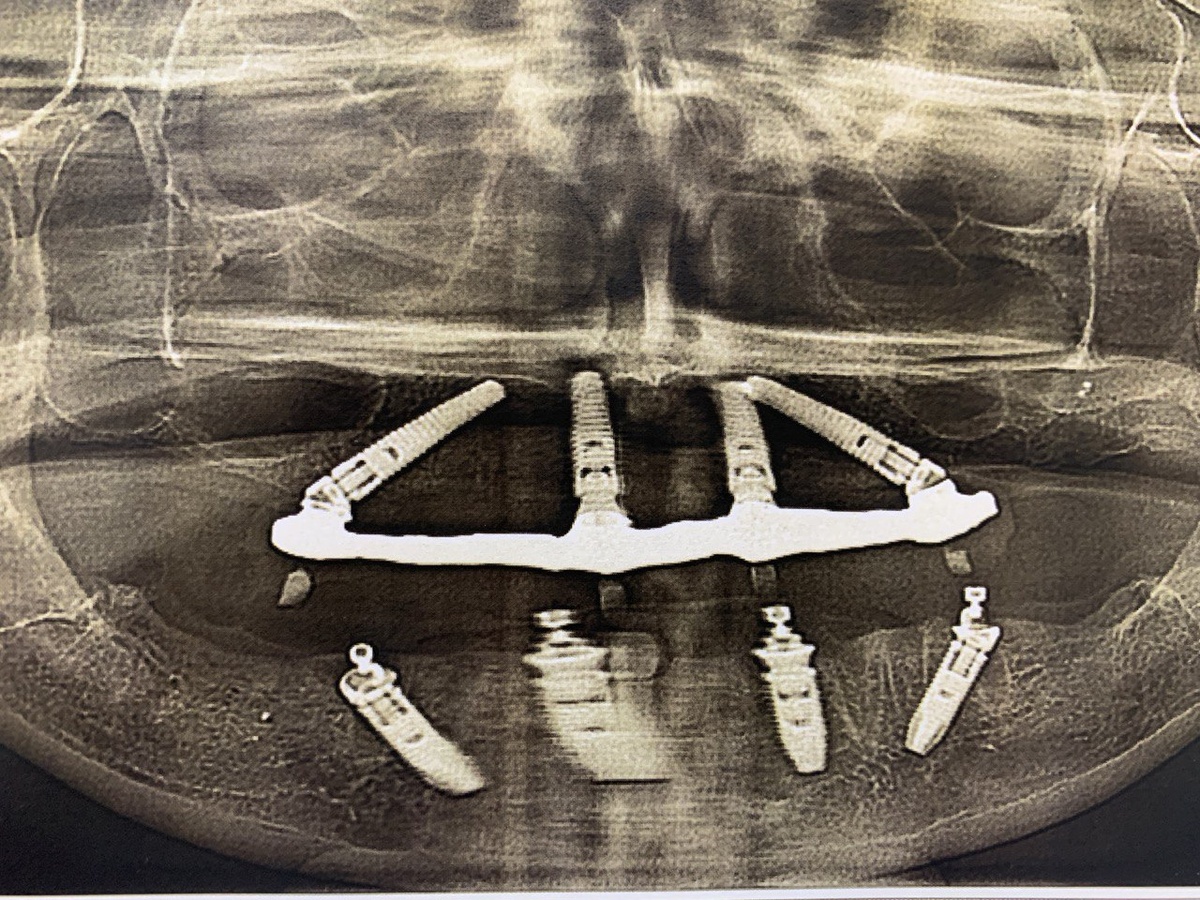

Мой снимок челюсти. На эти импланты прикручены коронки. Это и есть мои зубы

Вот он-то и сделал мне обе новые челюсти. Уже не было этой эпопеи, растянутой на года. Это называется система имплантов All-on-4.

✅✅Пуру слов о самой системе имплантации. Бывает на 4-ёх и 6-ти имплантатах на каждую челюсть.

Сначала пациент делает ЗД КТ-зубов. Врач в специальной программе расчитывает положение будущих имплантов. Учитывается всё - расстояние до носовых пазухов, строение сустава, состояние кости, общая симметрия лица и многое другое.

Неважно где росли вырванные зубы, врач ставит импланты в те места, какие выбраны в программе.

В обоих челюстях теперь только импланты. Швейцарские титановые Nobel. Самые дорогие, которые можно себе поставить в Москве. Я уже как-то писала про это статью, там про сами импланты рассказано. Так что, в моей крови титан, как говорится.